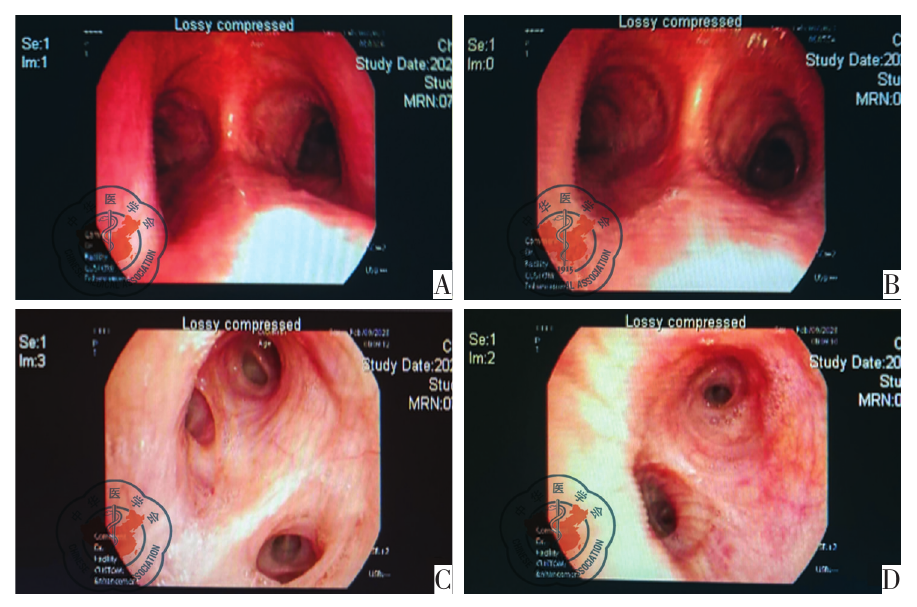

图2 电子支气管镜检查图。图A、B为支气管镜检查提示主气管管壁黏膜光整;图C、D为各级支气管壁黏膜可见白色分泌物,炎性改变